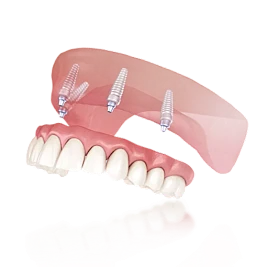

На верхней челюсти зафиксирован аппарат Хаас. Создано место для клыков, проведена подготовка к постоянному прикусу. Междисциплинарное лечение: хирургия и логопедия

- Фиксация аппарата Хаас (верхняя челюсть)

- Расширение и создание места для клыков